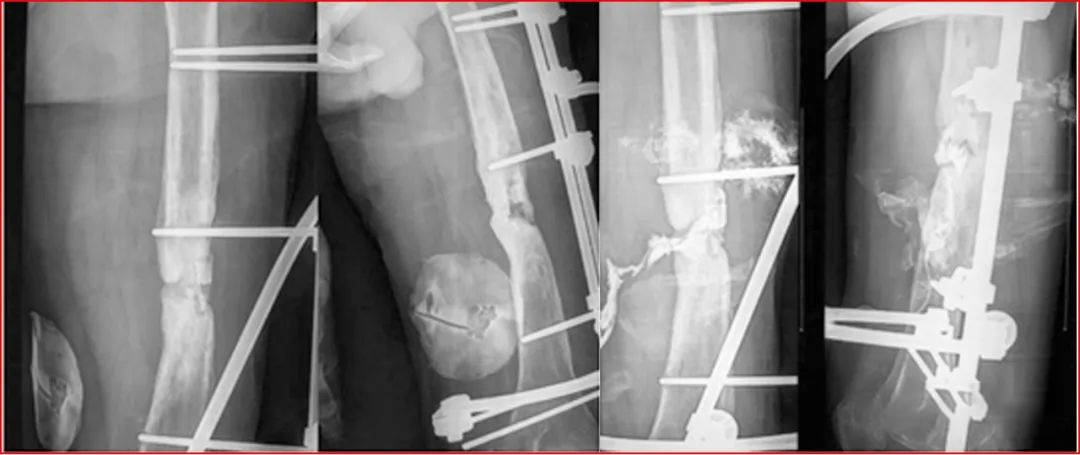

病例一 男,34岁,因火器伤致右小腿开放性粉碎性骨折,在当地医院应用带锁髓内针固定,创面皮肤感染坏死,髓内针外露。病灶清除后留有20cm长的胫骨缺损和6×12cm皮肤缺损。应用骨段与皮肤延长及加压固定和创面换药等综合外科措施治疗。创面肉芽新鲜后,应用皮肤牵伸术逐步修复创面;

病例二 患者,男,23岁,患者主因“右小腿外伤术15个月余”入院。患者11月前车祸致右小腿开放骨折,多次手术清创,胫腓骨缺损约18cm,胫前肌群和腓骨肌群缺损。诊断:①右胫腓骨骨缺损;②右胫腓骨延长术后。治疗周期约两年,拆除外固定。